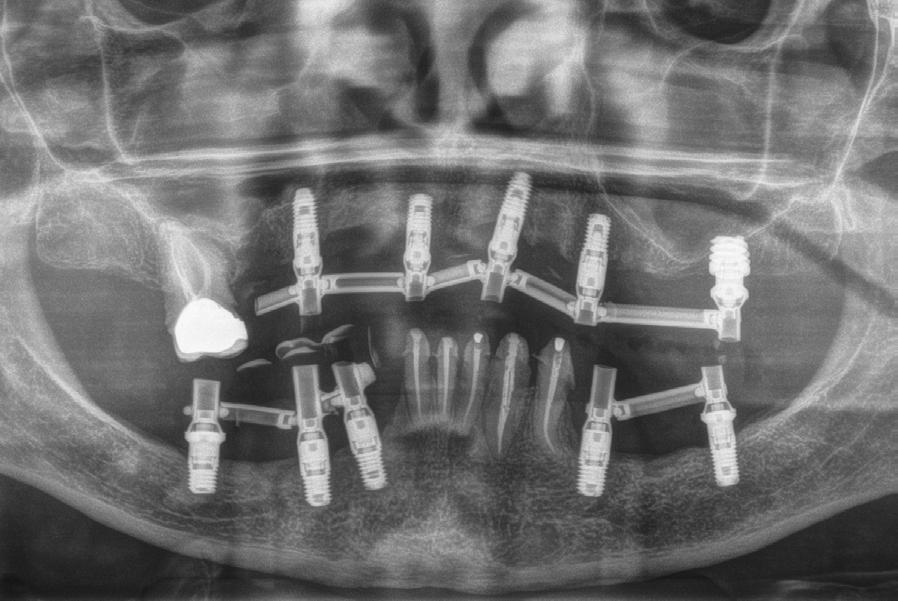

Figura 1. Radiografía inicial del caso donde observamos varios implantes con periimplantitis en el arco superior e inferior en diferentes estadios, incluso un implante que ya se ha perdido en la zona del incisivo lateral superior izquierdo y en el cuarto cuadrante.

190. Junio 2024 13

Figura 6. Radiografía postoperatoria tras las explantaciones y regeneración con PRGFENdoret de las zonas afectadas donde no era posible colocar nuevos implantes en la misma fase quirúrgica, así como colocación de otros implantes para iniciar la renovación del caso. Se mantuvieron tres implantes superiores provisionalmente para soportar la prótesis provisional.

Figura 9. Radiografía con las prótesis de carga inmediata.

Extracción atraumática de implantes afectados

Figura 12. Radiografía final con las prótesis, a los 3 años de seguimiento, con la estabilidad de todos los implantes, sin nuevas pérdidas óseas asociadas.